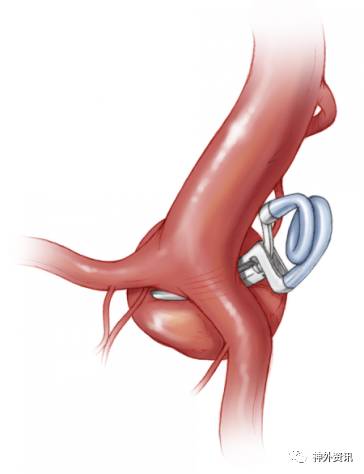

图1:一例典型的ICA分叉部动脉瘤,穿支血管绕着瘤顶走形。插图为术后CTA,可见术中使用了串联夹闭技术,同期夹闭一个小的脉络前动脉瘤。